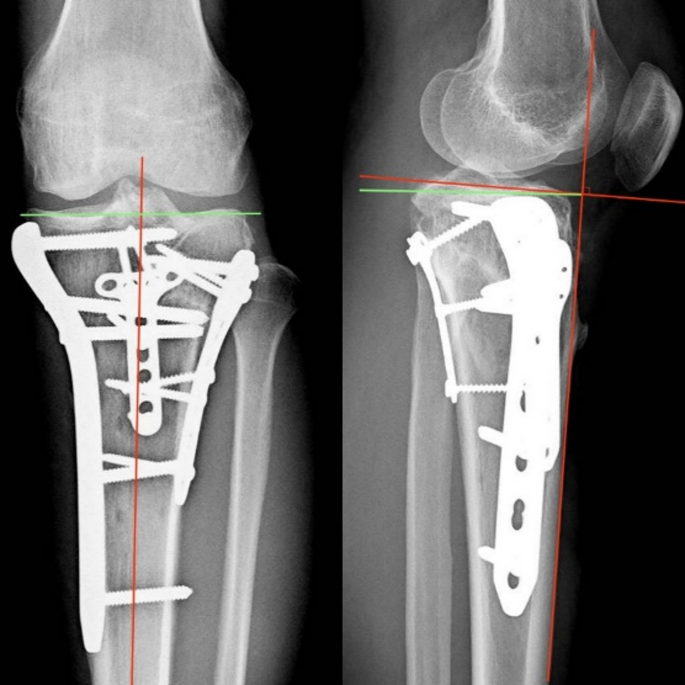

Case

A 32-year-old male patient involved in a traffic accident presented with a tibial plateau fracture as revealed by X-ray and CT scan (Fig. 5). The fracture was classified as Schatzker VI, and all three columns fracture. A 3D printing technique was employed to create a 1:1 solid prototype of the fracture. Surgeons performed in vitro simulation of the surgery using the model as guidance. During the actual operation, the model aided in achieving satisfactory fracture reduction and fixation, with the plate and screws positioned correctly. An 8-month follow-up X-ray demonstrated a well-aligned tibial plateau with visible callus formation. The Rasmussen score at this point was 23, indicating a good outcome, and the patient did not experience any surgical complications during this period (Fig. 6).

X-ray images at the 8-month follow-up, mTPA = 88.9°, PSA = 2.7°.